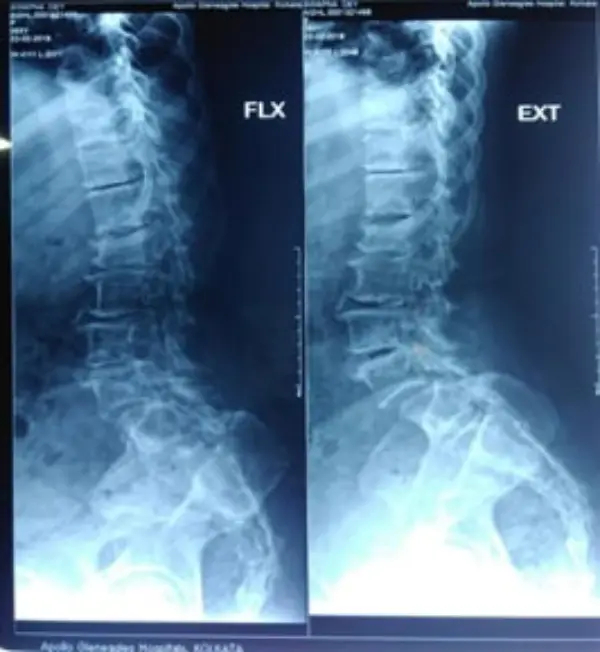

67 years old female presented with the complaints of low back ache radiating to posterior aspect of thigh for past 1 year. History of urinary incontinence (+) for the past 6 months & symptoms worsened for the past 2 months. She had difficulty in sitting, standing and walking on her own, and was totally dependent on care giver.

Diagnosis: Degenerative scoliosis

Treatment: D11 to L5 instrumented deformity correction, decompression and fusion.

Outcome: Patient was started on osteoporosis medications and has significant relief from leg symptoms. She is now an independent woman taking care of her activities of daily living.